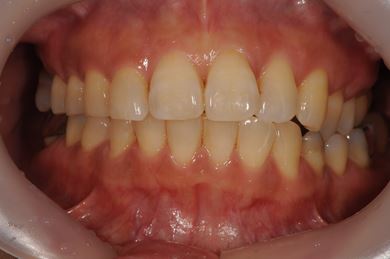

骨再生インプラント治療+セラミック治療+歯肉歯槽骨整形

| 性別/年齢 | 女性 / 42歳 | ||||||||||||||||||||||||||||||||

| 主訴 | インプラント治療を受けたい。 | ||||||||||||||||||||||||||||||||

| 治療方針 | 左上奥欠損部分をインプラント治療にて機能的・審美的回復を行う。 | ||||||||||||||||||||||||||||||||

| 治療内容 | インプラント2本(ソケットリフト)、メタルボンドセラミック3本(メタルボンド用土台1本)、歯肉歯槽骨整形 | ||||||||||||||||||||||||||||||||

| 総治療費 | 1,227,713円 | ||||||||||||||||||||||||||||||||

| 治療期間 | 11ヶ月 |